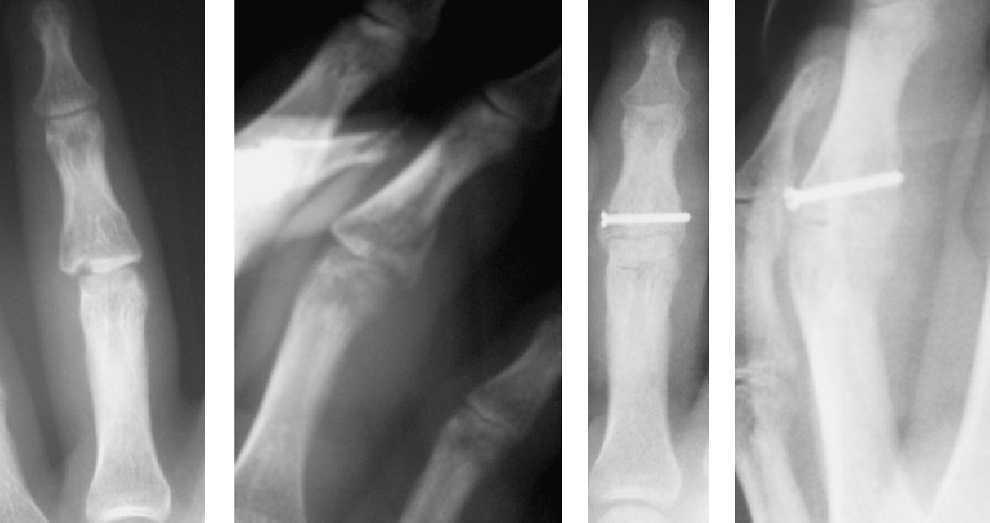

Para llevar a cabo esta técnica se realizó una selección según las características de los pacientes y el tipo de fractura. Es imprescindible que sean pacientes colaboradores y las fracturas subsidiarias de este tipo de tratamiento fueron fracturas inestables que permitían conseguir una buena estabilidad mediante la osteosíntesis con tornillos, como fracturas condíleas de las falanges, fracturas diafisarias espiroideas u oblicuas largas de la falange, fracturas de la base de la falange, fracturas intraarticulares y algunas fracturas de la base del primer metacarpiano (figura 1,figura 2,figura 3,figura 4).

Figura 1. Fractura oblicua larga extraarticular de la falange media del dedo medio.

Figura 2. Fractura de la base de la falange media del dedo anular.

Figura 3. Fractura de cóndilo de la falange proximal del dedo índice.